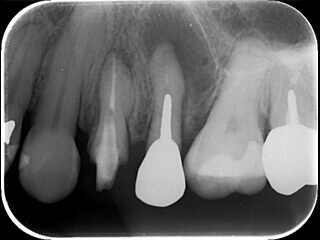

症例4 土台が大きくて治療できないようだ

15

太い金属(白く写っている部分)が入っており、その先の骨が溶けてます。

16

太い金属を安全に外し根の治療を終えました。骨は再生しています。